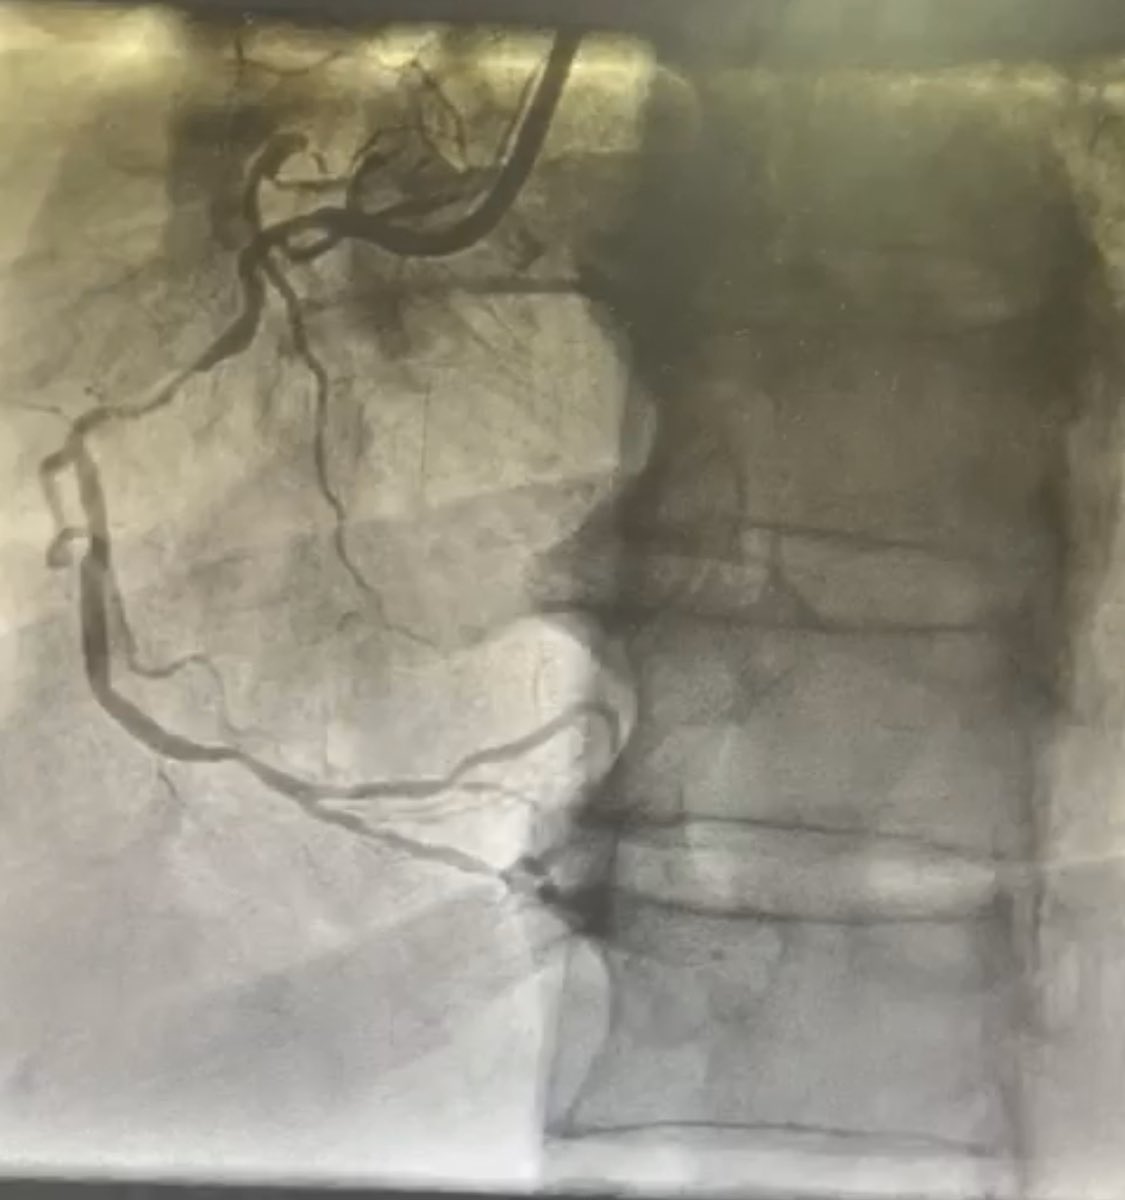

This ACS patient was in cardiogenic shock yesterday. We performed an Impella @ProtectedPCI with #RotaPro and #cullotte stenting. So rewarding to see him doing very well on the normal ward... 👍